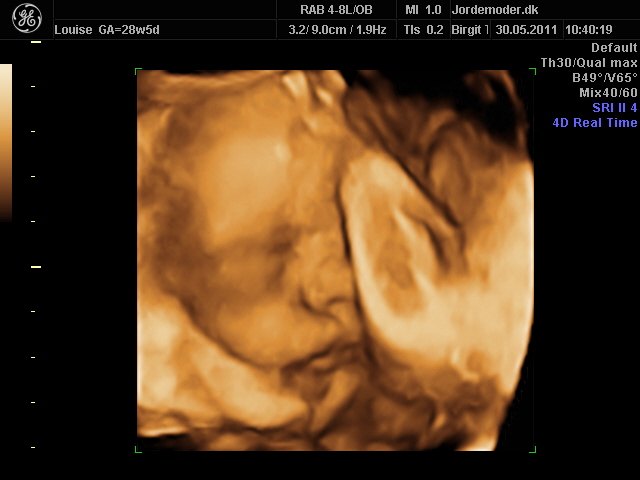

Så kom vi til 3d scanning igår. Lillepigen er slet ikke så stor som egen Jm kønnede hende HELDIGVIS! 1500 gram ca vejer hun nu, 28+6....

Hun har den fineste mund, jeg er helt misundelig på de smukker læber hun har.¨Ja hun er jo alt i alt bare dejlig, og jeg har ikke engang set hende sådan helt rigtig endnu.... Også har hun nogen gode runde kinder....

I skal ikke snydes for billeder af vores lille skønhed...